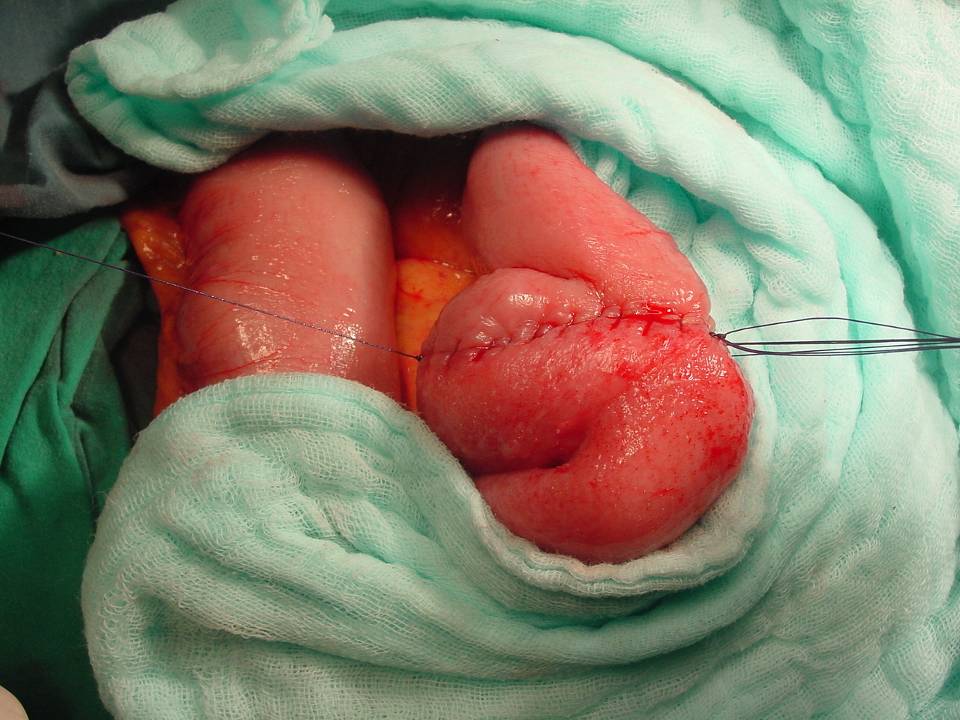

Konvansiyonel Radyoloji

• Kontrastlı grafilerde oral yolla verilen baryumun kontrast ajan olarak kullanılması ile ince barsak pasaj grafileri çekilir.

• Opak maddenin geçiş süresi

• Opak maddenin takılması

• Lümende olabilecek doluş defektleri